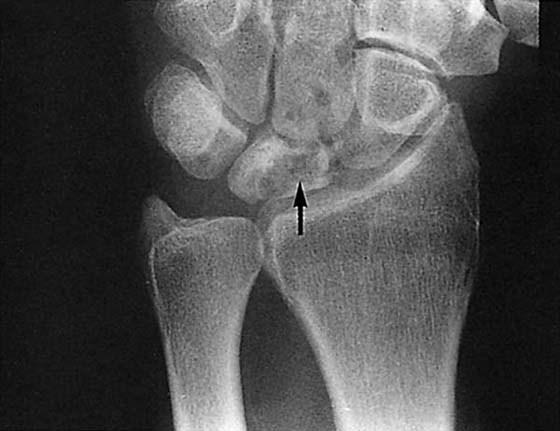

Bone density, which is evaluated grossly, may be normal, less than normal (osteopenia), or greater than normal (osteosclerosis). Osteopenia is most often encountered in the elderly and is known as senile osteoporosis when associated with advanced age. Osteosclerosis occurs in conditions such as avascular necrosis (AVN) (Fig. 13-2), fracture healing, and metabolic bone disease.2 Plain films may reveal discrete or diffuse bone lesions, including primary or metastatic bone tumors, infection, and metabolic bone disease (Fig. 13-3). The cortical integrity is carefully inspected for evidence of acute fracture (Fig. 13-4) and the joint alignment evaluated for subluxation or dislocation.3 Abnormalities of the articular surface and cartilage joint space also are documented. Narrowing of the cartilage space may indicate arthritis, resulting from degeneration, inflammation, infection, or trauma (Figs. 13-5 and 13-6).4 Finally, the soft tissue shadows are evaluated for irregularities. Any evidence of calcification (Fig. 13-7), foreign bodies (Fig. 13-8, online),5 or soft tissue masses must be correlated with the clinical findings.

Figure 13-4 This posteroanterior view of the wrist shows a fracture of the proximal third of the scaphoid (arrow) with an associated cyst.